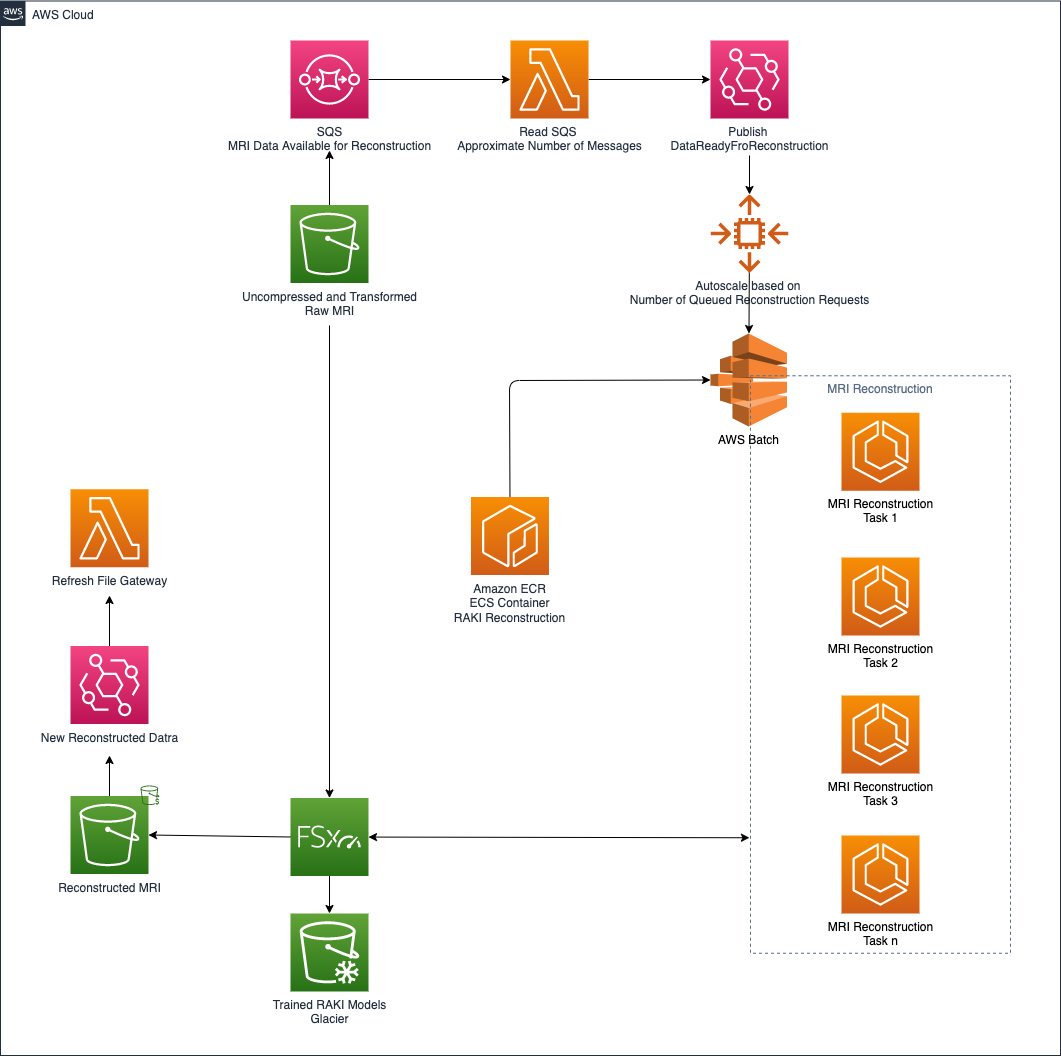

The following figure shows the architecture that realizes the neural model development and container creation.

In this architecture, Amazon SageMaker is used to develop the RAKI neural model, and simultaneously to create the container that is later used to perform the MRI reconstruction.

Then, the created container is included in the fully managed Amazon Elastic Container Registry (Amazon ECR) repository so that it can then spin off reconstruction tasks.

Fast data storage is guaranteed by the adoption of Amazon FSx for Lustre. It provides sub-millisecond latencies, up to hundreds of GBps of throughput, and up to millions of IOPS. This approach gives SageMaker access to a cost-effective, high-performance, and scalable storage solution.

The MRI reconstruction based on the RAKI neural network is handled by the architecture shown in the following diagram.

With the same architectural pattern adopted in the decompression and preprocessing layer, the reconstruction layer automatically scales up and down by analyzing the depth of the queue responsible for holding all the reconstruction requests. In this case, to enable GPU support, AWS Batch is used to run the MRI reconstruction jobs.

Amazon FSx for Lustre is used to exchange the large amount of data involved in MRI acquisition. Furthermore, when a reconstruction job is complete and the reconstructed MRI data is stored in the target S3 bucket, the architecture employed automatically requests a refresh of the storage gateway. This makes the reconstructed data available to the on-premises facility.